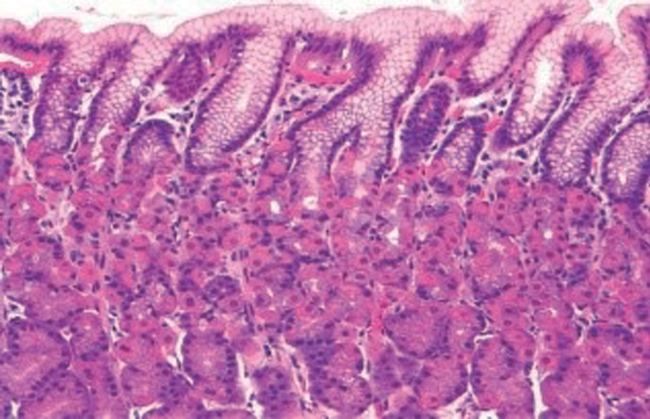

La mucosa oxíntico-fúndica en tanto, está constituída por glándulas redondeadas con células parietales y principales (Figura 2).

Las foveolas sólo representan un 10% del espesor total de dicha mucosa.